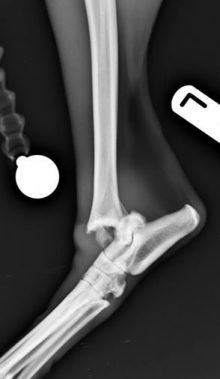

Hock Fracture Repair in Dog with Osteochondritis Dissecans

Repair of hock fracture secondary to osteochondritis dissecans of the medial talar ridge This hock fracture was secondary to ...